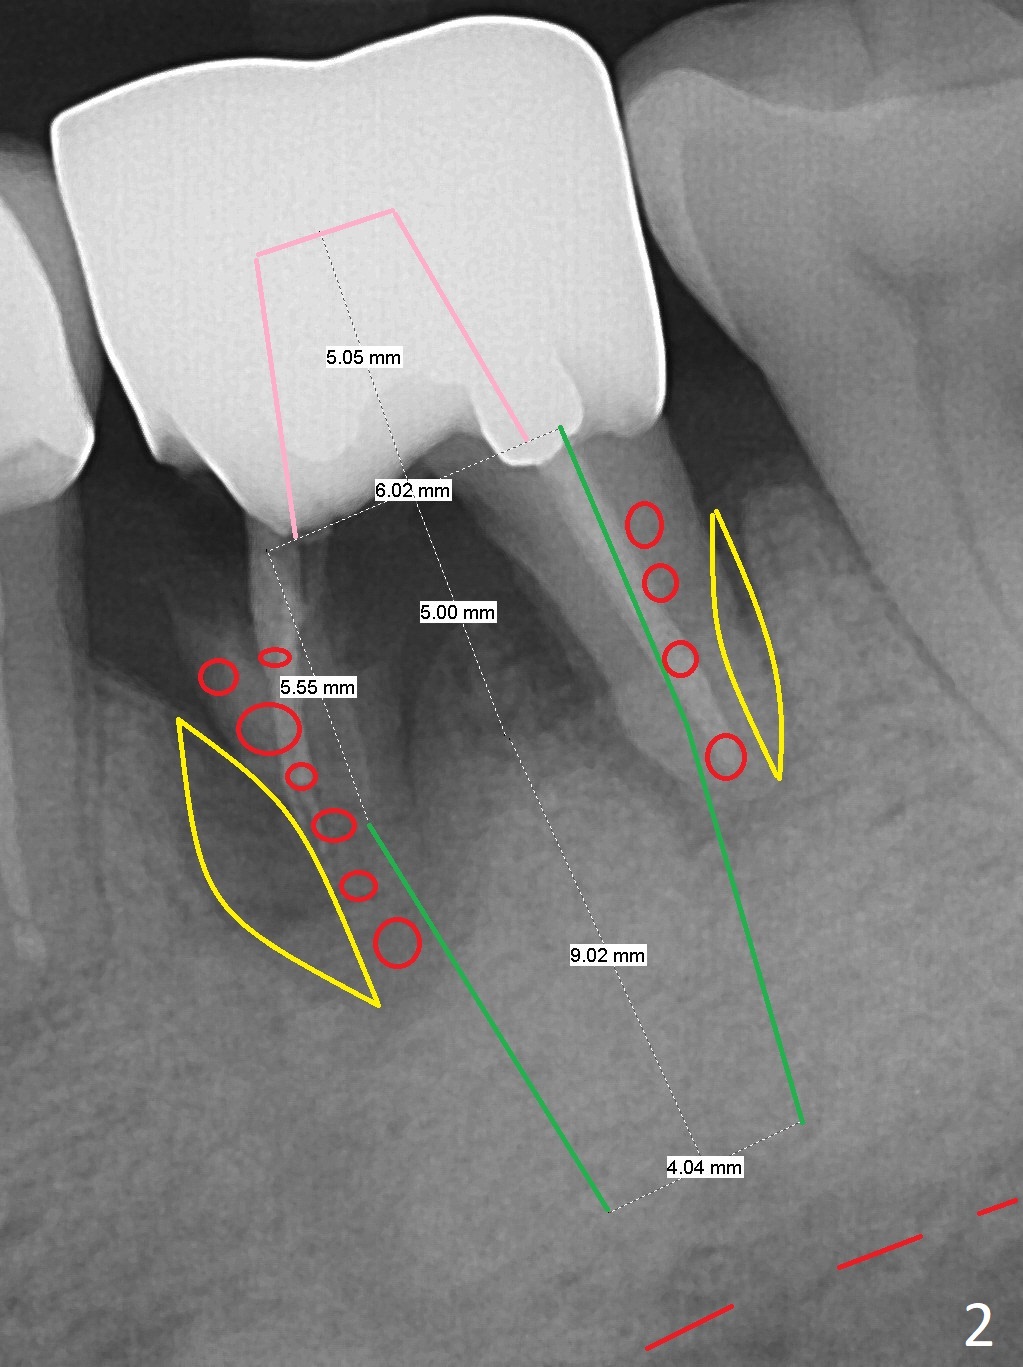

A 64-year-old man feels that the lower right 1st molar irritates the tongue. The mesial root fragment is sharp lingually (Fig.1). Initial osteotomy depth is 14 mm (gingival margin, Fig.2), as lingual as possible (Fig.3 CT taken on 01/21/2011).